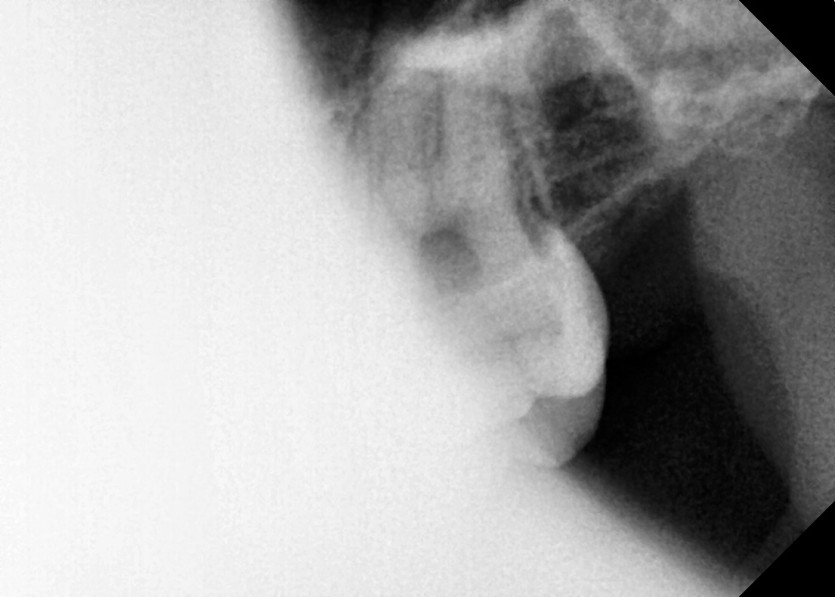

#18,28,38,48 사랑니 발치

구강 외과 전문의가 당일 발치했습니다.